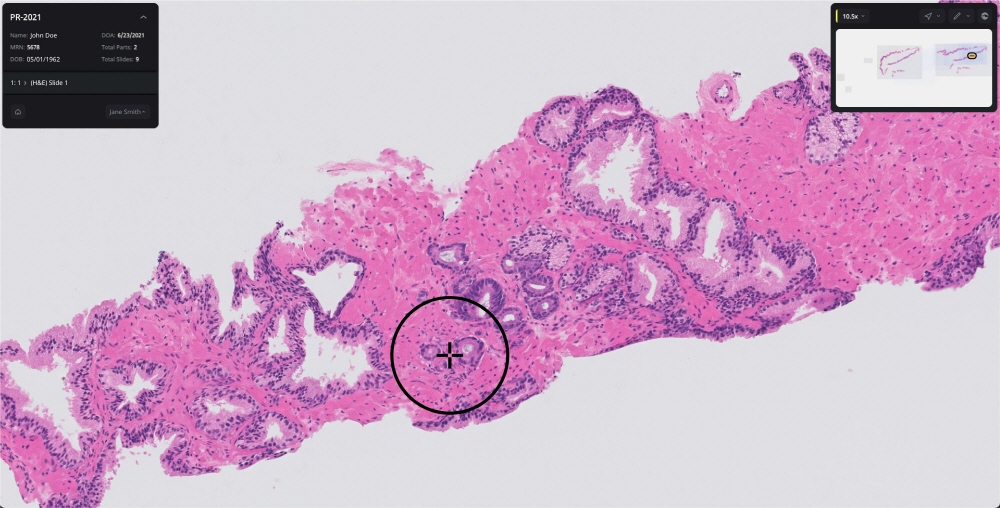

남성 생식기인 전립선에 발생하는 전립선암은 비흑색종 피부암을 빼고 미국 남성에게 가장 많은 암으로 암으로 인해 사망하는 남성 사망 원인도 상위권에 위치하고 있다. 2017년 설립된 AI 기업인 페이지(Paige)는 9월 21일 회사 전립선암 검출용 AI인 페이지 프로스테이트가 혁신적인 의료 기술에 대한 신청(De Novo)에 따르면 FDA는 승인을 얻었다고 보고했다. 발표에 따르면 생검된 전립선 조직 슬라이드 이미지를 분석해 암을 특정하는 AI로 FDA 승인을 받은 건 페이지 프로스테이트가 처음이다.

승인에는 FDA가 전문의 16명이 참가한 임상시험 결과를 평가했다. 이 시험은 악성종양이 있는 전립선 생검 슬라이드 사진 171장과 양성 슬라이드 사진 365장을 포함한 슬라이드 527개가 사용되어 각 전문의는 각각 슬라이드를 페이지 프로스테이트 어시스트 있음과 없음으로 분석했다.

테스트 결과 페이지 프로스테이트는 암 검출율을 89.5%에서 96.8%로 7% 포인트 향상시킨 한편 양성 종양 검출율에 영향을 주지 않았다는 걸 확인했다. 또 페이지 프로테스테이트 지원을 받은 의사는 위음성 진단이 70% 거짓, 긍정적인 진단이 24% 감소했다며 이런 효과는 전문의 경험과 검사는 원격 여부 등에 좌우되지 않았다고 한다.

FDA 의료기기 방사선 보건센터에서 체외 진단과 방사선 보건 부문 디렉터인 팀 스텐젤(Tim Stenzel) 박사는 페이지 프로스테이트에 대해 병리학과 전립선암 등 질벼잉 의심되는 조직 생검을 매일처럼 진단하고 있다며 AI가 생검 스캔 이미지에서 암이 의심스러운 영역을 특정하는 건 적절한 병리학 치료로 이어질 진단에 도움이 될 것이라고 설명했다.